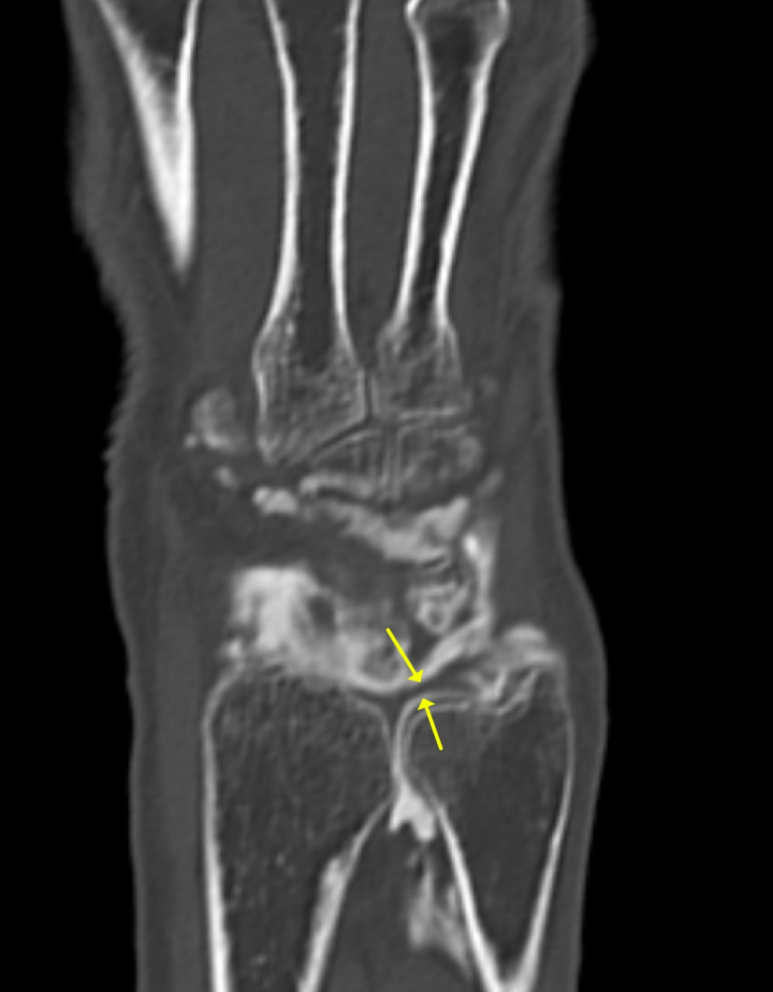

TFCC 파열을 진단하는

가장 확실한 골든 스탠다드는

관절에 조영제를 직접 주사한 뒤 검사하는

**'MRI 관절 조영술'입니다.

관절 주머니에 밝은 조영제를 넣으면

주변 구조물이 훨씬 선명하게 보이거든요.

노란색 화살표 친

**'삼각섬유연골'은

**'손목 관절'과

'원위요척관절' 사이에 있는데**

연골이 파열되면

그 틈으로 조영제가 새어 나가는 것을

직접 눈으로 확인할 수 있습니다.

@ https://doi.org/10.1186/s12891-020-03321-2

원래는 TFC로 막혀있어야 할

손목 관절과 원위요척관절이

파열로 틈이 생기면서

서로 연결되는 것이죠.